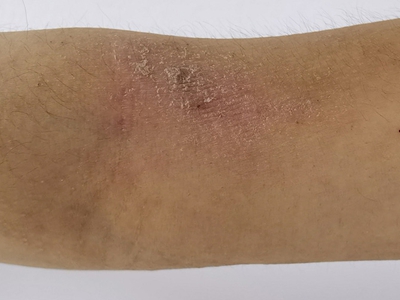

干性湿疹症状图片

干性湿疹又称乏脂性湿疹、裂纹性湿疹,多发生在秋、冬、春三季,由气候干燥、皮肤水分脱失、皮脂分泌减少所致,以皮肤干燥、干裂伴脱屑为主要临床表现。多见于老年人,好发于小腿,也可发生于双上肢等部位。

干性湿疹表现为皮肤干燥,有细裂纹,呈淡红色,浅表皲裂性皮肤类似“碎瓷”样。部分患者会出现瘙痒,不断抓挠后容易出现浅表糜烂、出血及结痂,轻者伴少量细碎的鳞屑,重者有较多的白色大片鳞屑脱落。